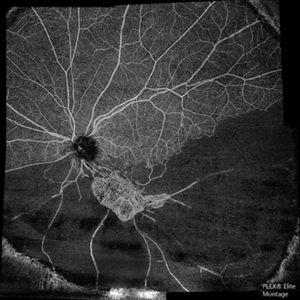

The Barren Field

A 59-year-old man with DM for 18 years operated for mature cataract. Post op left eye had a visual acuity of 20/80. Wide field swept source OCTA revealed gross vessel wipe out in inferior hemi quadrant with branching out neovascular frond inferior to disc with terminal loops, The patient underwent Anti VEGF injection followed by OCTA guided sectoral retinal photocoagulation.Image J software used here to generate reverse image that sharply delineates the non perfusion are

Photographer: Sandeep Kumar

Imaging device: Optical coherence tomography system Zeiss Plex Elite 9000

Condition/keywords: hemi CRVO